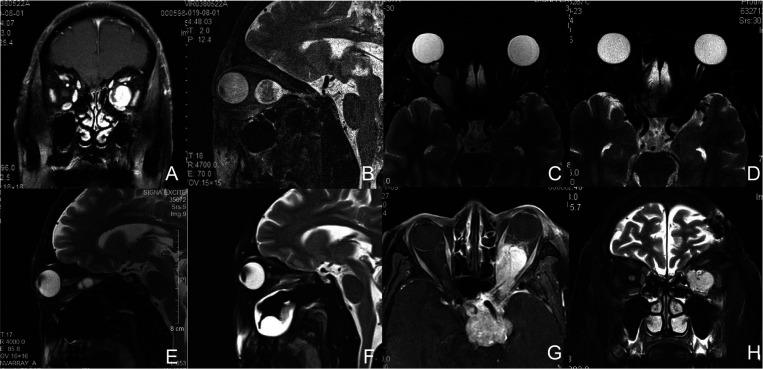

Four primary and one recurrent tumor were identified. The mean patient age was 50 (range, 29-64) years. One tumor was located lateral to the optic nerve, one central and three medial. A complete surgical resection was obtained in four primary cases and a partial resection was achieved in the recurrent case. The MRM was retracted using three different techniques: (1) an infant eyelid speculum creating an operative window between the medial and inferior rectus muscle, (2) external MRM disinsertion transconjunctivally, (3) a four-handed technique performed transseptally by two surgeons. Transient postoperative ophthalmoplegia was recorded in four cases and transient ptosis in one. Three patients completely recovered in 2-3 months while one undergoing MRM disinsertion ended up in restricted strabismus at 15-month follow-up. No other long-term complications have been noted in all five patients with a mean follow-up of 22 (range, 14-32) months. No patients with primary tumors have required additional surgery for tumor recurrence.

共发现4例原发性肿瘤和1例复发性肿瘤。患者平均年龄为50岁(范围29 - 64岁)。1例肿瘤位于视神经外侧,1例位于中央,3例位于内侧。4例原发性肿瘤实现了完整手术切除,复发性肿瘤实现了部分切除。采用三种不同技术牵拉MRM:(1)使用婴儿眼睑撑开器在鼻下直肌之间创建手术窗口;(2)经结膜外MRM断腱;(3)两名外科医生经鼻中隔采用四手操作技术。4例患者术后出现短暂性眼肌麻痹,1例出现短暂性上睑下垂。3例患者在2 - 3个月内完全恢复,1例接受MRM断腱术的患者在15个月随访时出现斜视受限。5例患者平均随访22个月(范围14 - 32个月),均未发现其他长期并发症。所有原发性肿瘤患者均未因肿瘤复发而需要再次手术。